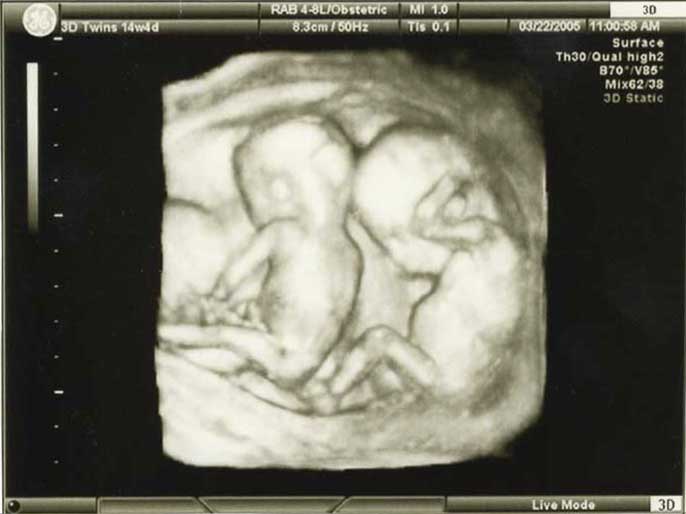

3D/4D HD LIVE

Στο ιατρείο μας προσφέρουμε υψηλής ευκρίνειας 3D και 4D τεχνολογία απεικόνισης του εμβρύου. Η τεχνολογία αυτή αποτελεί ένα ακόμα σημαντικό διαγνωστικό όπλο στη φαρέτρα του προγεννητικού ελέγχου, ενώ ταυτόχρονα ενισχύει την ανάπτυξη του δεσμού ανάμεσα στους μελλοντικούς γονείς και το μωρό τους.